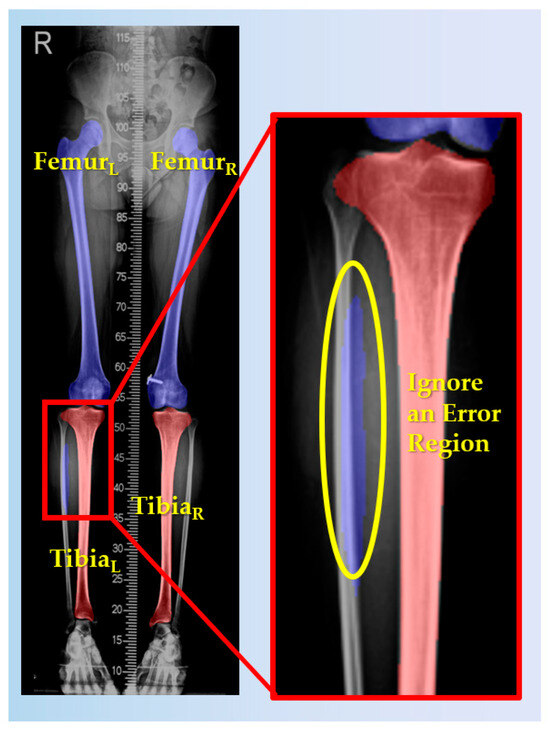

2.3.1. Femur and Tibia Segmentation

- i.

- Select the two largest femur and tibia regions:Let be the segmented image, where for femur and for tibia.

- ii.

- Identify connected regions:where represents connected components of femur and represents connected components of tibia with denoting the index of each connected component and j = 1, 2 specifying femur(j = 1) or tibia (j = 2)

- iii.

- Select the two largest regions:where and are the selected femur regions and and are the selected tibia regions.

- iv.

- Calculate the centroids of each femur and tibia regions:where the selected regions .

- v.

- Classify, based on centroid coordinates: